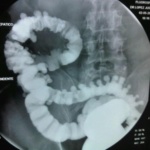

Los tipos especiales de exámenes de rayos X llamados estudios de contraste utilizan tintes con base de yodo o materiales de contraste, como el bario, junto con las radiografías para que los órganos aparezcan en la radiografía y obtener mejores imágenes. Por ejemplo, las radiografías del tracto gastrointestinal inferior, normalmente llamado examen de enema de bario, se emplean para tomar imágenes después de que el intestino se llena con sulfato de bario. Otro estudio, un pielograma intravenoso, usa un colorante especial para examinar la estructura y el funcionamiento del sistema urinario (uréteres, vejiga y riñones).

Radiografías del tracto gastrointestinal inferior (enema de bario): se puede restringir su alimentación durante algunos días antes del estudio. Se usan laxantes, enemas, o ambos, para vaciar el intestino grueso. Para el estudio, usted se acuesta y será sujetado a una mesa. Se toma una serie de radiografías. Luego el líquido de bario se coloca dentro del intestino por medio de un tubo pequeño y blando ubicado en el recto. El líquido se siente frío. Se procede a tomar más imágenes mientras la mesa le inclina a usted en diferentes posiciones. Esto ayuda a que el bario se mueva por los intestinos de modo que puedan verse en las radiografías. Tiene que permanecer acostado inmóvil y contener la respiración cuando se toma cada imagen.

Para obtener imágenes más claras, por lo general se realiza un examen con “contraste doble”. En este examen se usa una cantidad más pequeña de líquido de bario más espeso. Después que el bario está adentro, se hace ingresar aire en sus intestinos. Esto puede causar una sensación de hinchazón y malestar, junto con la ganas de vaciar los intestinos.